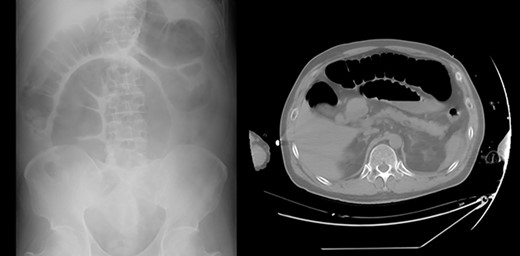

A 61-year-old man complained of progressive vision loss on the right side and visual field loss on the left side of the ear. Head magnetic resonance imaging examination showed a 26 × 18 × 24 mm pituitary suprasellar cystic tumor with enhancement on T1-weighted images after gadolinium injection. The tumor contained septal-like structures consistent with craniopharyngioma. He had a history of glaucoma and chronic atrial fibrillation and was undergoing medical treatment. The pituitary gland was within the range of normal endocrine function before the surgery. Consequently, he underwent extended endoscopic transsphenoidal surgery. Pituitary function was lost and the pituitary stalk was amputated for complete tumor removal. On the day of surgery, he was diagnosed with CDI, showing polyuria (3640 ml) in 8 hours. He was started on intravenous vasopressin with an index serum sodium level of 140–145 (mEq/l) and oral rehydration therapy based on thirst (Fig. 1; Table 1). For hypopituitarism, glucocorticoid coverage was initially planned as 100 mg of intraoperative and postoperative hydrocortisone on the day of surgery, followed by intravenous administration of 50 mg for 2 days and 30 mg for 1 day. On the second day, he showed occasional episodes of vomiting, a symptom of hypopituitarism. As a result, parenteral hydrocortisone was increased to 80 mg that day and 50 mg on the fourth day. However, periodic vomiting continued, and despite the fasting period, the patient developed aspiration pneumonia on the third day, which progressed to severe sepsis on the fourth day (Table 1). Abdominal radiography and computed tomography revealed pseudo-intestinal obstruction as a direct cause of vomiting (Fig. 2). During multidisciplinary treatment for severe sepsis, he defecated on postoperative day 14, and abdominal radiography showed improvement of pseudo-intestinal obstruction. He was discharged on Day 79 with a prescription for oral glucocorticoid and intranasal desmopressin.